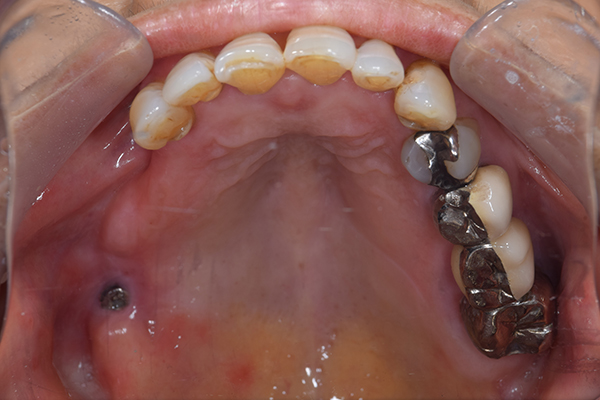

上下の入れ歯が外れやすくなったということでいらっしゃいました。 顎の骨はしっかりしていましたので、精密な型取りさえすればしっかりした入れ歯がつくれると思いました。 また下には6本歯が残っていましたが、虫歯になっている歯もありました。 かぶせ物のなかで大きな虫歯があった歯があり、1本だけ残せない状態でした。

上の入れ歯は確かに吸着は甘くなっていました。 また下の入れ歯はバネの一部が壊れており、安定感がなくなっていました。

精密な型取りの後、噛み合わせのチェックをしていきました。 かぶせ物も同時に作っていきました。

歯を並べた後、かぶせ物のフレーム作ってもらいました。先に歯を並べて理想の位置を決めておくことが大切です。

完成した入れ歯とかぶせ物です。 入れ歯への寛容度が高い患者様でしたので、 金属は使用せず、プラスチックのみで上は仕上げました。 下顎も歯は1本減ってしまいましたが、しっかり 入れ歯が維持できる様な構造にしました。

お口の中に入れた状態です。 見た目も最初とほとんど変わることなく作成できました。 維持や吸着に関しても問題ないようでした。